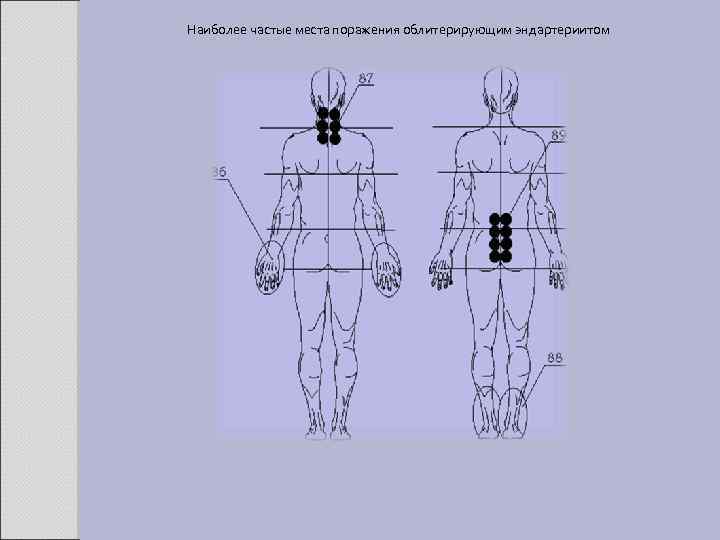

Наиболее частые места поражения облитерирующим эндартериитом